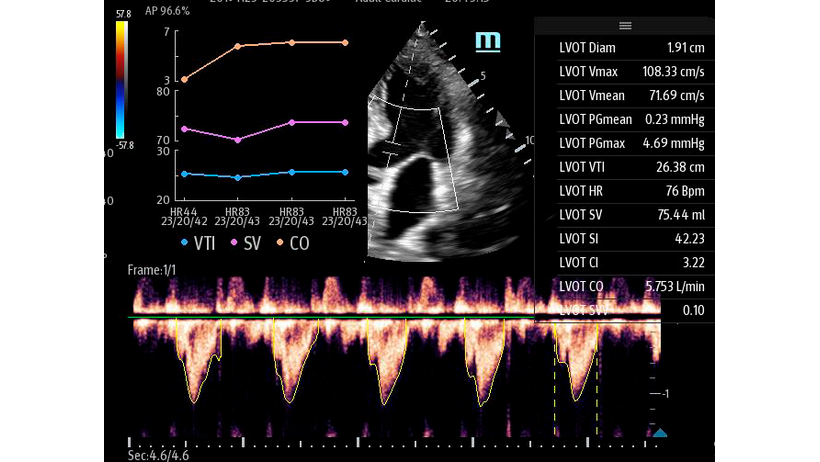

Автоматическая оценка потока выносящего тракта – Smart VTI

Чтобы использовать уравнение, нужно получить поток выносящего тракта левого желудочка в PW допплере — это достаточно кропотливая работа. В ультразвуковых системах Mindray Resona i9 эта задача решается автоматической оценкой потока выносящего тракта – Smart VTI.

Доктору остается получить 5-ти камерное сечение сердца и нажать одну кнопку на сенсорном экране. Прибор сам выберет расположение контрольного объема, получит спектрограмму и обведет спектр с расчётом всех показателей. Быстро и эффективно.